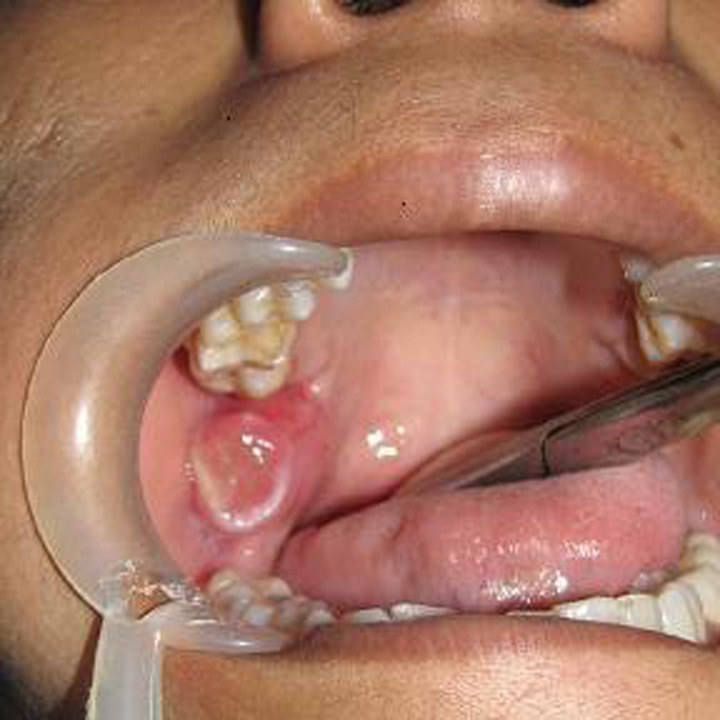

A 24 year old female patient reported to unit with complaint of mild swelling over right back tooth region. The swelling was associated with pain during mastication. There was no complaint of parethesia of any region. The lesion had appeared 11 months earlier as small nodule and gradually increased in size. The patient was otherwise healthy and had no significant past medical history and no other symptoms; her family history was also unremarkable. On examination an approximate 20 mm diameter mass was observed over the right retromolar region with overlying ulcerated mucosa due to impingement of upper right second molar while closing of mouth. The mass was firm, non tender and relatively mobile (Fig. 1).

Fig. 1.

Tumor mass over right retromolar area with overlying ulcer